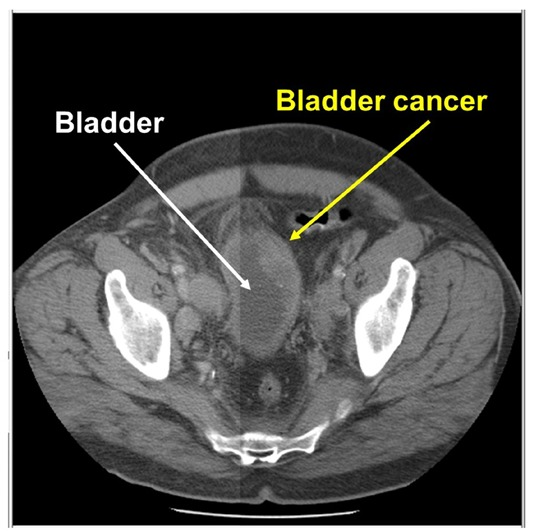

📌المقطعي المحوسب CT